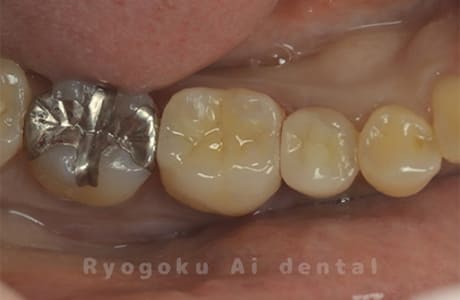

Case11

- 治療内容

- セラミッククラウン、セラミックインレー

-

- 治療費用

- 123,000円×2(セラミッククラン)、77,000円(セラミックインレー)

銀歯が取れて、ご来院された患者様です。奥歯2本をセラミッククラウン、手前の小臼歯をセラミックインレーで治療を行いました。